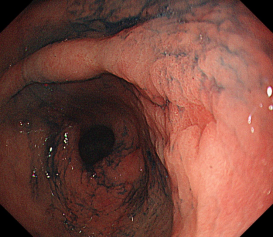

消化道早癌的病例展示(经内镜手术或活检证实):

胃窦印戒细胞癌